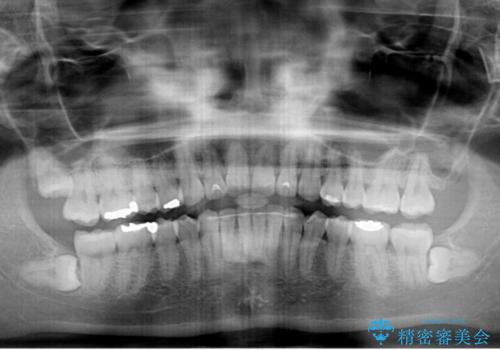

矯正治療の後戻り ガタガタになった前歯の部分矯正

もう少しデコボコを改善したかったのですが、ご本人の希望もあり、装置を除去しました。

後戻りを防止するため、舌側を細いワイヤーによる保定を行いました。